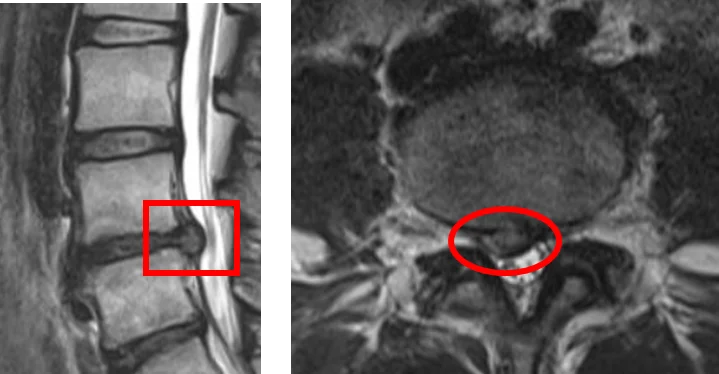

Межпозвночная грыжа на МРТ-снимке: сагиттальный (слева) и аксиальный (справа) срезы

По снимкам МРТ можно определить наличие/отсутствие дегенерации межпозвоночных дисков, состояние суставов, связок и нервных корешков, наличие/отсутствие воспаления. Это позволяет поставить точный диагноз.

МРТ-снимки позволяют диагностировать не только межпозвоночную грыжу, но и стеноз позвоночного канала, опухоли позвоночника, инфекции и переломы.